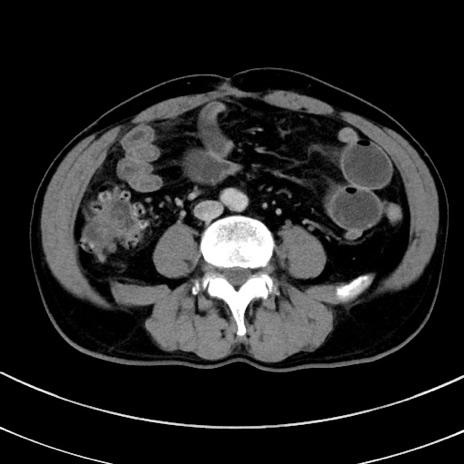

症例8(横断像)

【症例】 60歳代男性

【主訴】 黒色吐物

【現病歴】 4日前から嘔気自覚、2日前の朝食後にも嘔気あり、自分で手で嘔吐反射起こし嘔吐したところ血が混ざっていたため受診。

【既往歴】 5年前汎発性腹膜炎を伴う急性虫垂炎で手術、高血圧、前立腺肥大症、高脂血症

【身体所見】 腹部正中に手術癩痕あり 腹部平坦・軟圧痛なし膨満感あり

【データ】WBC 8400、CRP 4.54